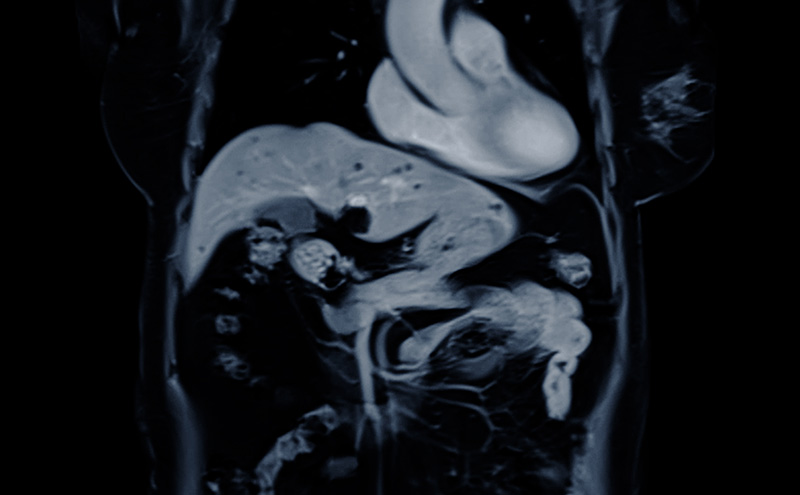

A previously healthy 64 year old female presenting 10 days post bladder sling repair operation with intractable vomiting, bilateral flank, and abdominal pain. Her vital signs are relatively normal, and her nausea improves with several treatments for nausea. Her exam reveals abdominal pain and flank pain, so a point of care ultrasound is done, showing moderate hydronephrosis right > left with hydroureter bilaterally and a foley balloon in a mostly decompressed bladder. She is admitted to urology for bilateral ureteral decompression and revision of her surgery due to physical obstruction of ureters.